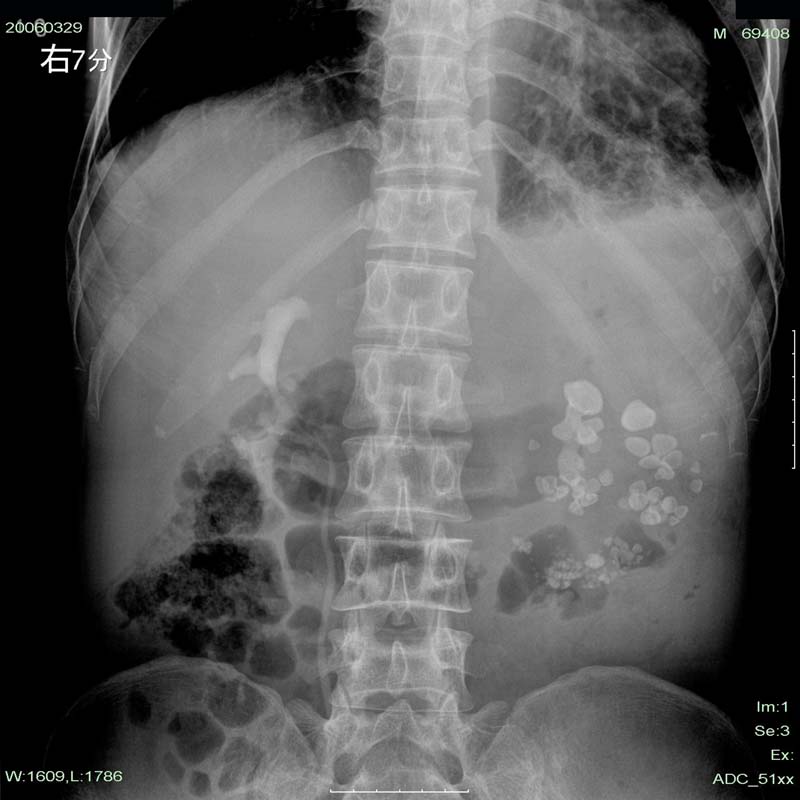

下午做的检查,第二天早上透视,左肾区仍未见造影剂显影。

我们放射科的前辈的意见和b超的差不多。

可是我个人认为是:左侧自截肾伴左肾排泄功能丧失。

这个是左肾多发性结石伴重度积水。其与肾自截不同的是:肾自截呈全肾钙化,肾脏缩小.本例肾内密度增高影呈颗粒状,肾影增大.故不支持肾自截

本例造影过程中结石位置,大小等都未有明显改变。左肾体积明显增大,与肾自截相反。且无钙化。故支持向医生的观点。

从这份片上我们可以看到左肺心影响后肺纹理增强紊乱,可见蜂窝状改变,且左侧肋膈角变顿,胸膜粘连。可能肺有慢性肺病(结核?)。从腹部片看,左肾区多发结石影可以肯定,但其下部可见一些斑条状致密影,不能排除是钙化。左肾轮廓并未显示清楚且位置较右肾还低。所以本人认为左肾多发结石并重度积水要考虑,尚需考虑肾自截可能,建议加拍胸片明确胸部情况并行双肾ct扫描。